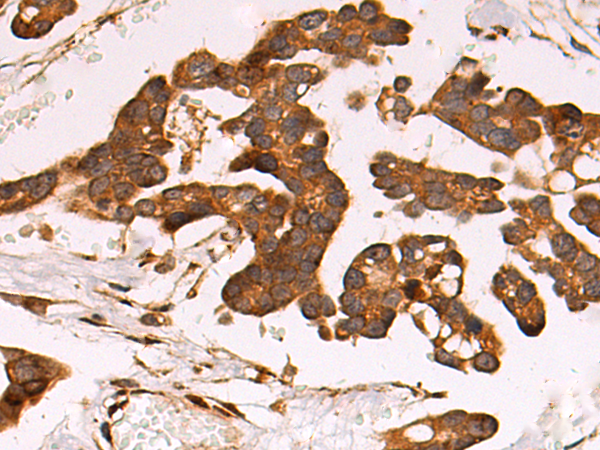

Product Image

- The image is immunohistochemistry of paraffin-embedded Human colorectal cancer tissue using P06835(LRP1 Antibody) at dilution 1/50. (Original magnification: ×200)